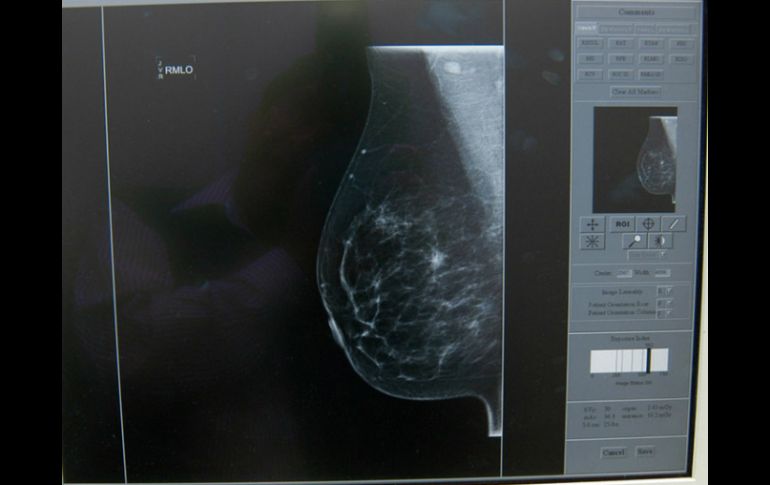

Tecnología | Este prototipo podrá detectar la enfermedad en etapas tempranas Desarrollan en México chip para detectar cáncer de mama Este prototipo podrá detectar la enfermedad en etapas tempranas Por: EFE 25 de noviembre de 2014 - 10:17 hs El chip tiene un grado de sensibilidad mayor que el de métodos tradicionales de detección, ya que alcanza hasta un 90 por ciento. NTX / ARCHIVO CIUDAD DE MÉXICO (25/NOV/2014).- Científicos mexicanos crearon un prototipo de microchip, a base de proteínas y nanopartículas de oro, capaz de detectar cáncer de mama en etapas tempranas, informó el Consejo Nacional de Ciencia y Tecnología ( Conacyt). El doctor Rodolfo Hernández Gutiérrez, responsable del proyecto, comentó que antes de la fabricación del chip era necesario conocer qué tipo de moléculas o proteínas de la sangre de pacientes con cáncer son detectables en etapas tempranas de la enfermedad. Para ello, Hernández y un grupo de investigadores de la Unidad de Biotecnología Médica y Farmacéutica del Centro de Investigación y Asistencia en Tecnología y Diseño del Estado de Jalisco (Ciatej) hicieron un análisis comparativo entre muestras de sangre de mujeres con cáncer de mama en etapa II, y otras de mujeres que no lo tenían. Los científicos descubrieron dos proteínas en la sangre de las mujeres con cáncer -alfa-1 antitripsina y alfa-2 glicoproteína (ambos descubrimientos de Hernández Gutiérrez publicados en artículos científicos y con solicitud de patente)- que no estaban presentes en la sangre de las mujeres sanas. Los investigadores concluyeron que ambas proteínas son exclusivas del cáncer de mama y con ellas se pudo dar paso al desarrollo de un primer prototipo de chip de diagnóstico temprano. Hernández señaló que se analizó la sangre de mujeres con cáncer de mama en etapa II debido a que durante dicha etapa esta neoplasia es asintomática, "y cuanto más oportuno sea el diagnóstico la paciente tiene mayores posibilidades de responder satisfactoriamente a un tratamiento". El microchip tiene dimensiones aproximadas de 1.5 centímetros de ancho por siete de largo y 1.5 de profundidad, y se asemeja a una pequeña caja con un hueco al centro. Ahí será colocada la muestra del paciente, junto con tres soluciones con distintos compuestos y nanopartículas de oro. En conjunto evidenciarán la presencia de cáncer mediante la coloración de una membrana. "Si ésta muestra manchas negras, significa que el paciente tiene un proceso canceroso; si no se manifiestan, quiere decir que la mujer no tiene la neoplasia", apuntó el especialista. El chip tiene un grado de sensibilidad mayor que el de métodos tradicionales de detección de cáncer de mama (autoexploración, examen clínico de los senos y mastografía), ya que alcanza hasta un 90 por ciento. "Habría que hacer más pruebas con más dispositivos para cerciorarse de que este porcentaje es igual en todas las pruebas", advirtió el doctor. Asimismo, a diferencia de una biopsia que se realiza cuando la mujer ha sido diagnosticada con esta neoplasia o el médico necesita corroborar la naturaleza de algún abultamiento o tumor, el chip no es invasivo ya que no se necesita extraer quirúrgicamente nada de la paciente, solamente una muestra sanguínea. Actualmente, el grupo está en proceso de estandarización para definir la mejor forma de colocar las proteínas dentro del dispositivo (goteo, inyección a presión), así como la cantidad óptima de reactivos. Esta etapa estará terminada en enero de 2015 y se espera que ya se cuente con más prototipos para que sean transferidos a instituciones públicas de salud, señaló en un boletín el Conacyt, al que pertenece el Ciatej. Temas Descubrimientos Ciencia médica Cáncer de mama Conacyt Lee También Estudio chino revela una mutación que eleva riesgo de alzhéimer Entrevista: Gerardo Cárdenas muestra “Lo que no se ve” Sociales: El Eco de lo Invisible, una exposición fotográfica sobre las huellas ocultas del cáncer NASA confirma si el cometa 31/ATLAS amenaza la vida en la Tierra o no Recibe las últimas noticias en tu e-mail Todo lo que necesitas saber para comenzar tu día Registrarse implica aceptar los Términos y Condiciones